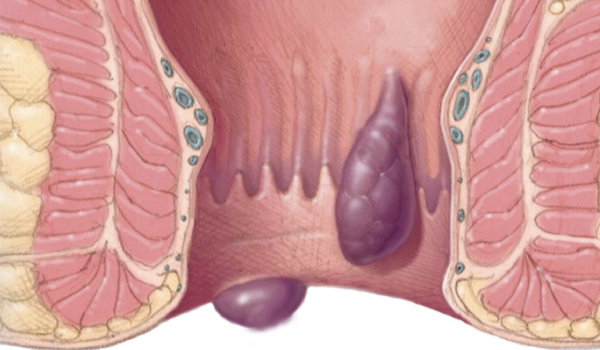

Extracción de hemorroides internas y externas causantes de sangrado rectal.

Estudio prospectivo observacional sobre la eficacia y resultados a largo plazo de la hemorroidoplastia láser en pacientes con hemorroides grado II al IV, con seguimiento de tres años.